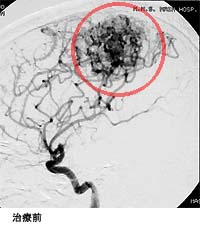

脳出血による半身麻痺と意識障害で発症した患者さまの治療前後の血管撮影を下に示します。(赤線内が脳動静脈奇形の部分)

手術中の血管奇形部分の写真。青丸部分に拡張した血管網が見られます。(下図)

(画像は、日本赤十字社医療センター 脳神経外科 野村竜太郎先生のご好意による)